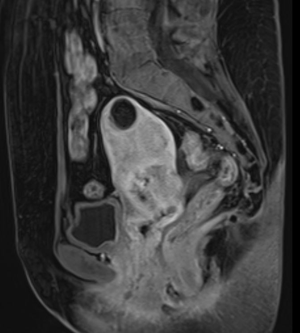

МР-диагностика рака тела матки

МР-диагностика рака шейки матки

МР-диагностика рака яичников